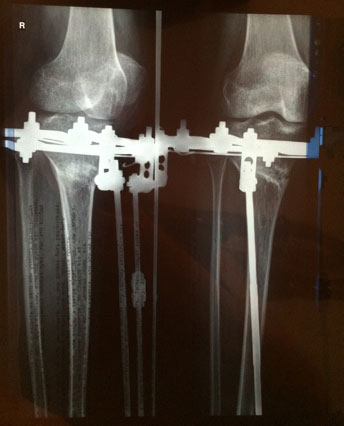

рентген от 16 октября.

Пора на снятие аппаратов!